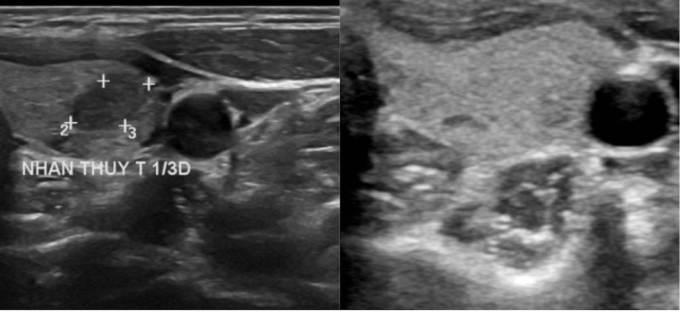

Khối u của chị Kiều trước điều trị (bên trái) và sau 12 tháng đốt sóng cao tần (bên phải) biến mất hoàn toàn. Ảnh: Bệnh viện Đa khoa Tâm Anh

Ngày 29/10,bác sĩ Khánh cho hay thông thường phương pháp điều trị ung thư tuyến giáp phổ biến là phẫu thuật cắt bán phần hoặc toàn bộ tuyến giáp. Sau đó người bệnh uống thuốc iốt để tránh ung thư tái phát và uống hormone tuyến giáp suốt đời. Trường hợp chị Kiều,khối u kích thước dưới 1 cm,cách xa vỏ bao tuyến giáp hơn 5 mm và siêu âm chưa thấy hạch di căn. Do đó,bác sĩ lựa chọn phương pháp đốt sóng cao tần (RFA) để bảo tồn tối đa tuyến giáp bệnh nhân.

Để điều trị cho chị Kiều,dưới hướng dẫn siêu âm bác sĩ đưa kim đốt xuyên qua da,tiếp cận khối u. Nhiệt từ dòng điện xoay chiều ở đầu kim đốt cháy các mô xung quanh gây hoại tử,theo thời gian u teo nhỏ dần.

Sau 20 phút đốt điện,khối u mất hoàn toàn,người bệnh xuất viện ngay trong ngày. Đến nay,sau một năm,u không tái phát,bác sĩ Khánh cho rằng kết quả này tương đồng với nhiều nghiên cứu trên thế giới. Ví dụ,nghiên cứu của Hội tuyến giáp Mỹ công bố năm 2022,tổng hợp các báo cáo về điều trị ung thư tuyến giáp bằng sóng cao tần RFA trên 1.770 bệnh nhân,cho thấy 79% trường hợp ung thư biến mất hoàn toàn,khoảng 0,4% nhân vẫn tiến triển sau đốt. Kết quả này được đưa ra sau thời gian trung bình 33 tháng theo dõi bệnh nhân đốt RFA.